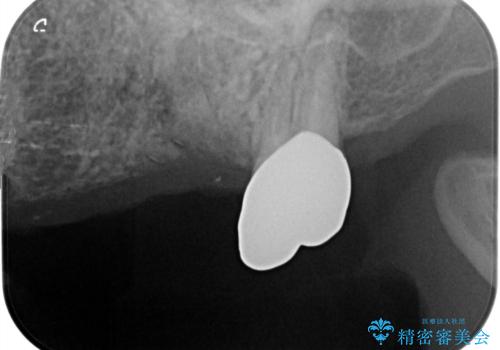

- 歯のないまま放置していた左上奥歯の咬合機能回復を求めて来院されました

咬合力が強く、入れ歯では周囲の歯も欠損状態になることが予想されたので、しっかりと咬合機能の回復のできる

インプラント治療を行うこととしました。